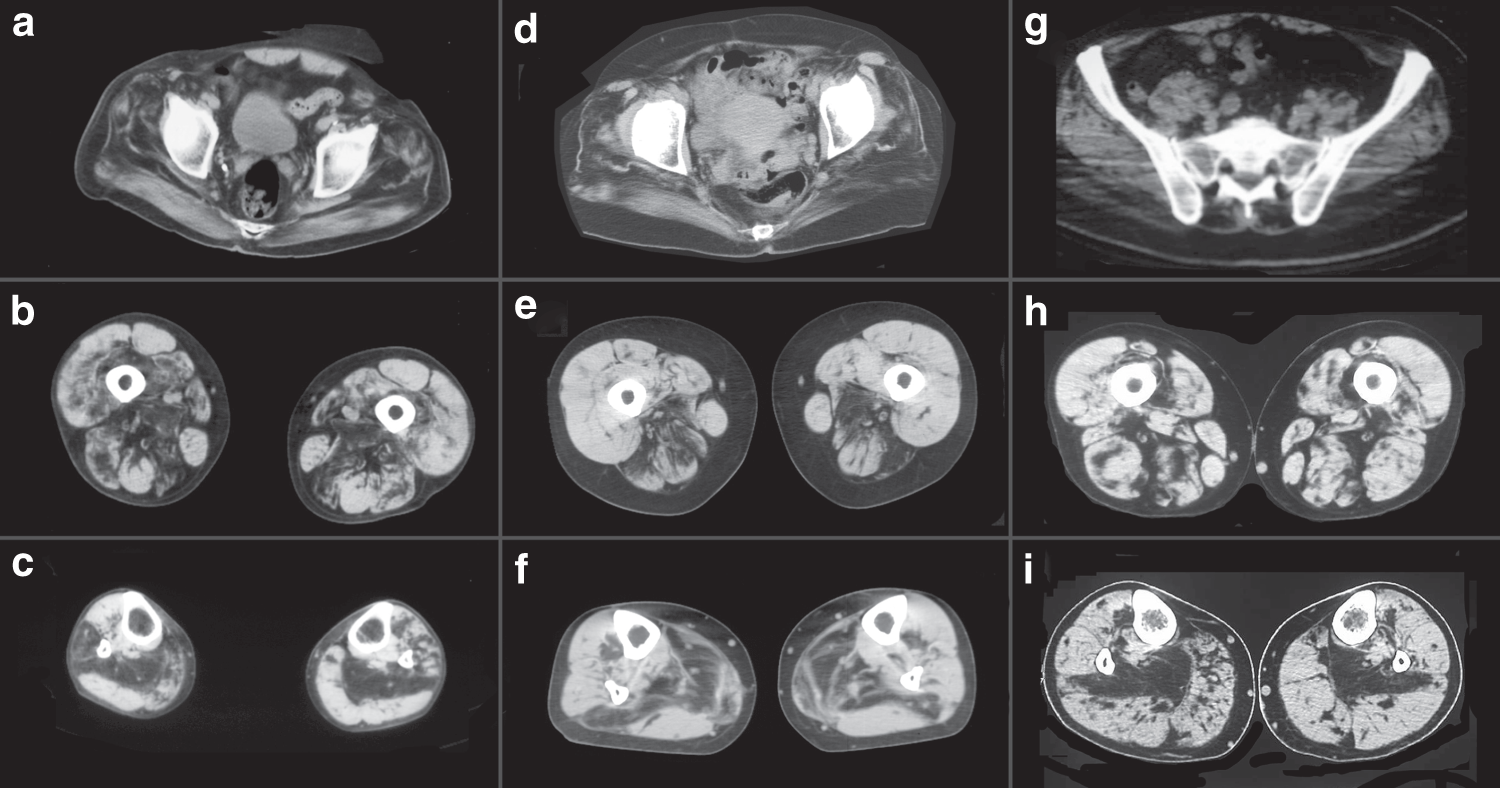

Fig. 2

Muscle imaging in myoglobinopathy. Muscle CT scan from individuals F1, II: 7 (a–c); F4, II: 4 (d–f); and F5, II: 6 (g–i) at the pelvic (a, d and g), mid-thigh (b, e, and h), and mid-leg (c, f, and i). At the pelvis, there is involvement of the gluteus maximus, medius, and minimus. At mid-thigh, there is preferential involvement of the posterior compartment, specially, of the adductor magnus, biceps femoris, and semimembranosus. At the mid-leg, the soleus is the first and most-affected muscle